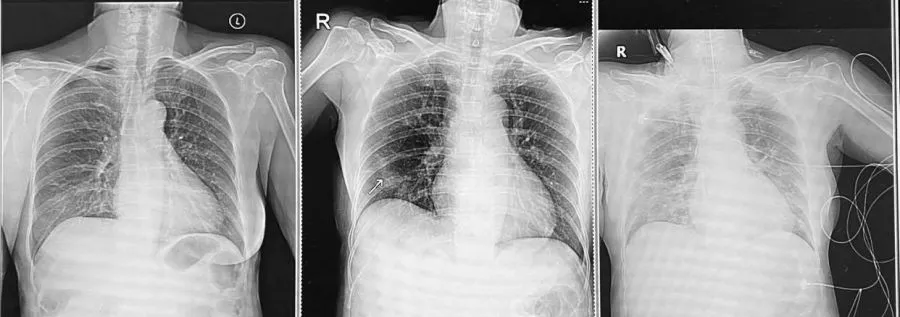

วันที่มาตรวจคุณป้ามีอาการคล้ายเป็นหวัดมา 6 วัน เอกซเรย์ปอดยังปกติ อีกวันถัดมาอาการปอดอักเสบชัดขึ้น คนไข้หายใจเหนื่อยจนระบบหายใจล้มเหลวอย่างรวดเร็วและใส่ท่อช่วยหายใจ ย้ายเข้าห้องไอซียู คนไข้อาการหนักมาก เข้าใจความรู้สึกของลูกที่รู้ทีหลังว่าแม่ตัวเองต้องมานอนไอซียูเพราะไม่ระวังเรื่องการกักตัว